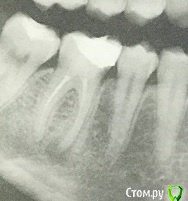

Craysley@rambler.ru Опубликовано 16 июля, 2016 Поделиться Опубликовано 16 июля, 2016 (изменено) Здравствуйте! Сегодня ходила на лечение зубного канала шестерки. Этот зуб до этого мне лечили лет 5 назад. Врач просверлил пломбу, кое-как добрался до корня зуба, вколол какие-то лекарства туда и установил временную пломбу. Сказал, что лекарство как должно постоять там хотя бы неделю. Однако, этим же днем, когда я жевала мягкую булочку, откололся кусочек стенки этого зуба.Вины стоматолога тут в любом случае нет, до этого там по линии разлома были две трещинки. Вроде с другой стороны тоже имеется трещина. Что теперь будет с зубом? Можно ли будет его восстановить пломбой? Прилагаю рентген зуба до сегодняшнего лечения. Изменено 16 июля, 2016 пользователем Craysley@rambler.ru Ссылка на комментарий

St. Опубликовано 16 июля, 2016 Поделиться Опубликовано 16 июля, 2016 До скола зубу тоже показана была коронка, т.к. он без нерва и с очень большой пломбой. С новой пломбой вы рискуете сломать стенку зуба на не прогнозируемую глубину. И тогда как повезет - или коронка или удаление зуба. 1 Ссылка на комментарий